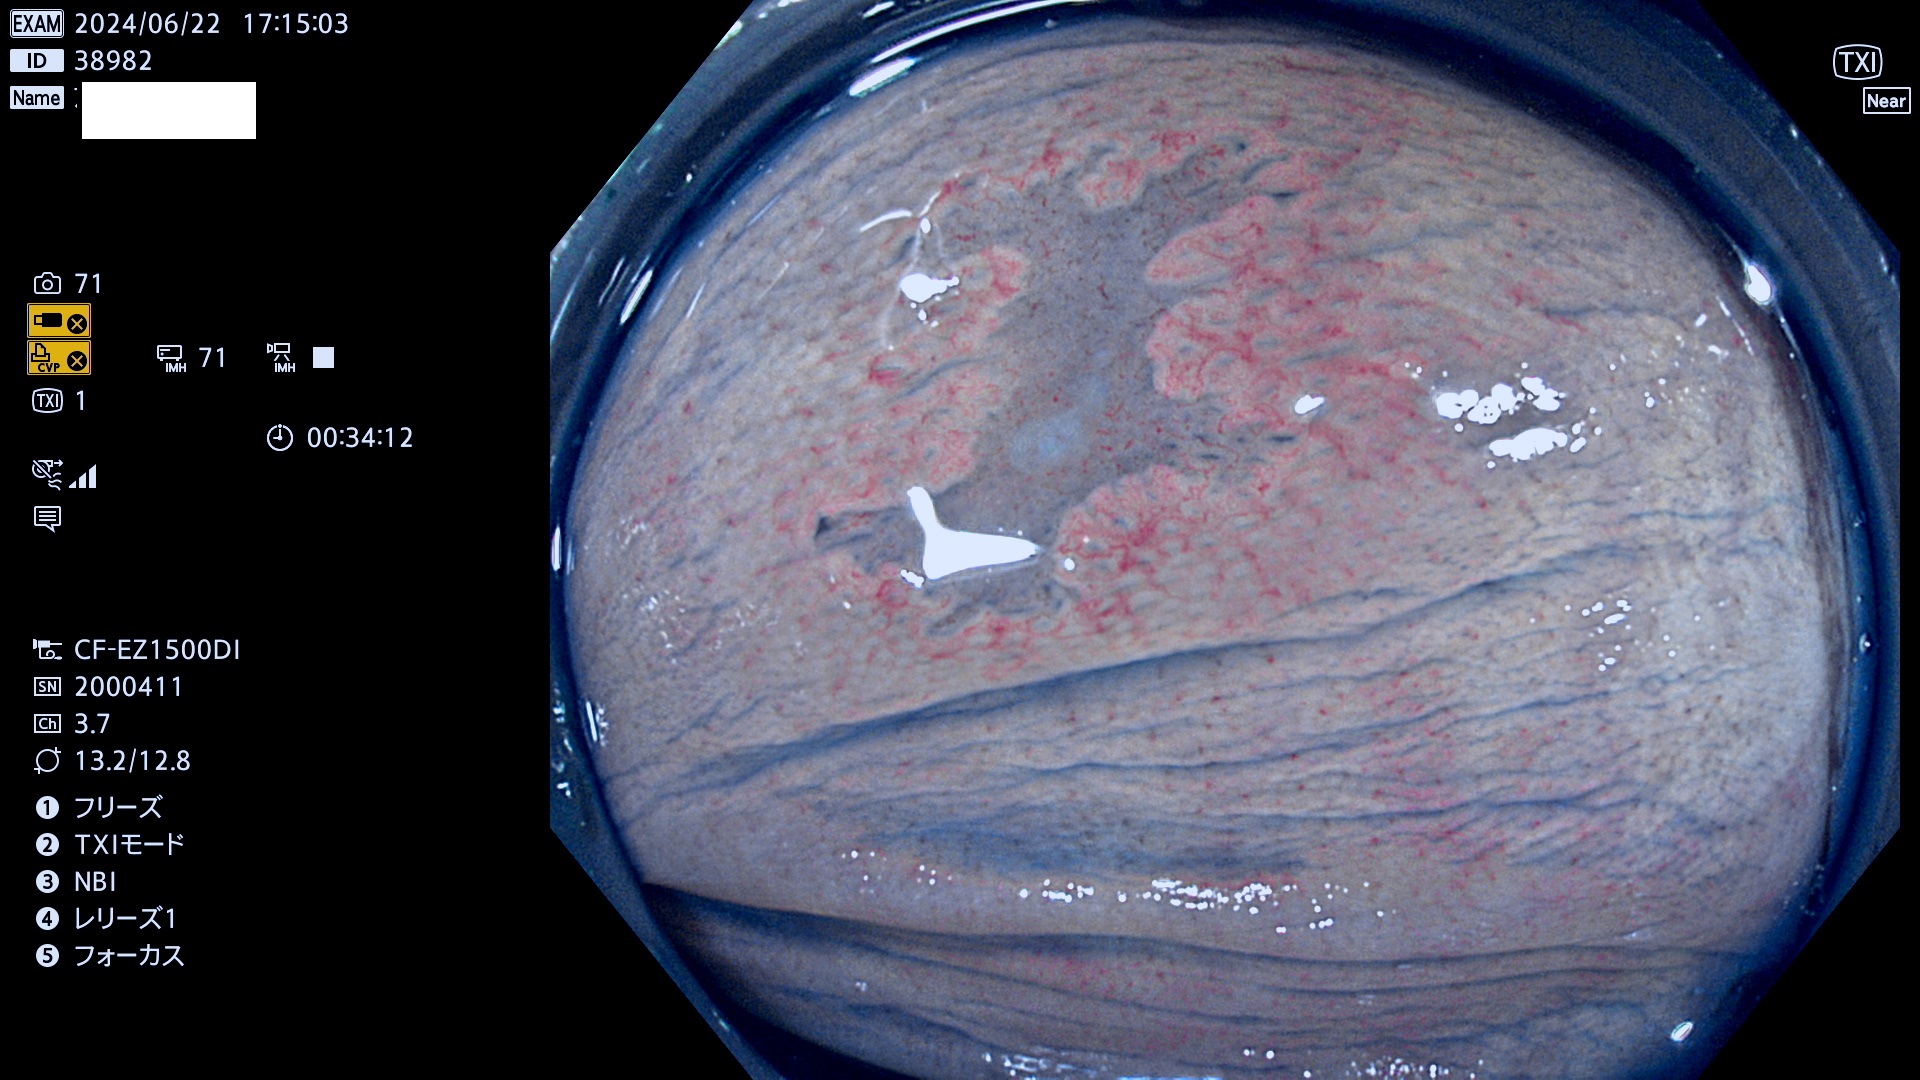

今週のUb、Uc型腺腫

完全に平坦な物をUb、陥凹している物をUcと呼びます。最も発見が難しく危険な病変です。

抽出の対象期間 2024年6月20日〜6月24の5日間(40件の検査)6件 (6/40=15%)